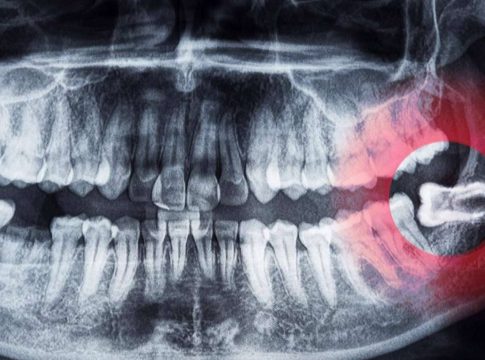

Las cordales o terceros molares son las últimas muelas que suelen aparecer en la boca a una edad comprendida entre los 17 y los 25 años.

En algunas personas, las cordales nunca llegan a brotar y, en otras, pueden causar problemas debido a su posición. En los casos de mayor gravedad, los especialistas recomiendan la extracción de los molares si existe algún cambio en la zona donde están esas muelas, por ejemplo: dolor, infección o quistes. Dicho procedimiento siempre debe ser realizado por un especialista en cirugía bucal y maxilofacial, ya que pueden presentarse complicaciones si el procedimiento no es correctamente realizado. Actualmente, existen clínicas de salud dental dedicadas a la extracción de cordales, como es el caso de Cibumaxi.

En este sentido, una de las causas más comunes para extraer las cordales son las infecciones como la pericoronitis o las caries. Asimismo, se recomienda en pacientes que presenten quistes, ulceraciones o traumatismos en las encías. La exodoncia también es habitual durante tratamientos de ortodoncia para la alineación de los dientes.

Los odontólogos también advierten que los terceros molares retenidos pueden causar graves problemas en la salud dental. Los dolores agudos, lesiones dentales y encías hinchadas son las consecuencias más frecuentes. Además, algunas personas pueden experimentar inflamación en la mandíbula, formación de quistes, tumoraciones, neuralgias y dificultad para abrir la boca.